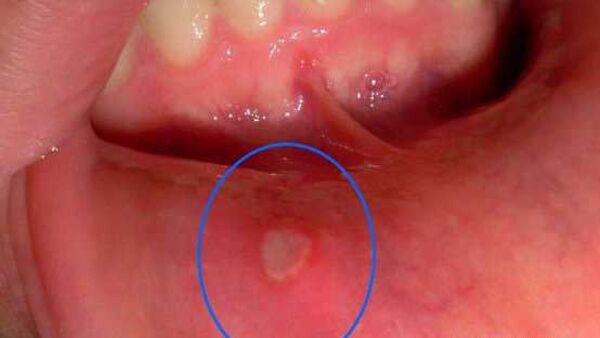

Cách trị nhiệt miệng bằng các loại rauCách trị nhiệt miệng bằng các loại rau - Nhiệt miệng khiến bạn khổ sở đế… Chuse24h Sức khỏe, Tư vấn sức khỏe10年前00600